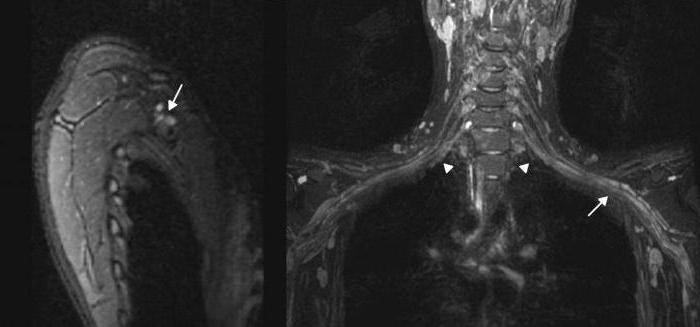

Современная диагностика плексита не вызывает затруднений. В большинстве случаев её проводит врач (травматолог, невропатолог или ортопед) на основе жалоб пациента и данных различных исследований, включая:

- рентгенографию;

- электромиографию;

- ультразвуковое обследование;

- магнитно-резонансную томографию.